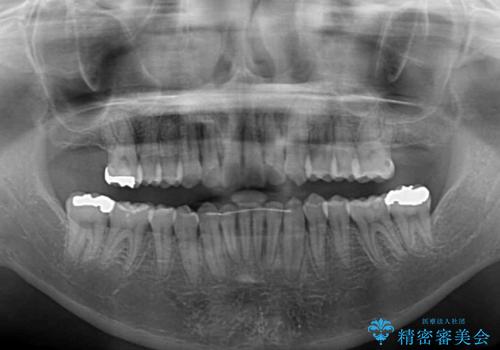

左右ともに、上顎第二大臼歯が欠損しており、下顎の第二大臼歯が十分に咬み合う歯がない状態のため、放置しておくと下顎の奥歯が挺出してくる可能性があります。

安定した咬み合わせを維持するためにも、将来的に上左右にインプラント補綴が必要となります。